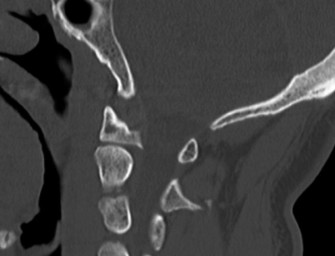

Upon his return five years later, the imaging profile was drastically different. Standing lateral radiographs now revealed a Meyerding Grade 2 spondylolisthesis at L5-S1, indicating that the L5 vertebral body had translated anteriorly by 25% to 50% over the sacral promontory. Furthermore, there was a noticeable collapse of the L5-S1 intervertebral disc space, signifying advanced degenerative changes secondary to the altered biomechanics and chronic instability. We also meticulously measured the patient's spinopelvic parameters on a standing 36-inch scoliosis cassette. His Pelvic Incidence (PI) was measured at 65 degrees (high), which mathematically dictates a higher Sacral Slope (SS) and Pelvic Tilt (PT). A high PI is a known biomechanical risk factor for the progression of spondylolisthesis, as it creates a steeper lumbosacral shear angle, placing immense anterior translational force across the compromised L5-S1 segment.

To evaluate the neural elements and the soft tissue structures, a comprehensive MRI of the lumbar spine without contrast was obtained. The T2-weighted sagittal and axial sequences confirmed the Grade 2 anterolisthesis and demonstrated severe bilateral foraminal stenosis at L5-S1. The exiting L5 nerve roots were severely compressed between the hypertrophied, fibrocartilaginous pseudarthrosis tissue of the pars defect dorsally, and the bulging, degenerated L5-S1 disc and superior endplate of S1 ventrally. Furthermore, the MRI revealed Modic Type II changes (fatty replacement of the subchondral bone marrow) in the adjacent vertebral endplates, confirming chronic biomechanical stress and discogenic degeneration. The central canal remained relatively patent, which is characteristic of isthmic spondylolisthesis, as the posterior neural arch is left behind during the anterior translation of the vertebral body.

When the patient returned five years later with a Meyerding Grade 2 isthmic spondylolisthesis, severe L5 radiculopathy, and MRI evidence of L5-S1 disc degeneration, the treatment paradigm shifted entirely to surgical intervention. The Meyerding classification grades the severity of the slip based on the percentage of anterior translation of the superior vertebral body over the inferior one: Grade 1 (0-25%), Grade 2 (26-50%), Grade 3 (51-75%), Grade 4 (76-100%), and Spondyloptosis (>100%). For a symptomatic Grade 2 slip that has failed conservative management (or in this case, progressed due to non-compliance), surgical stabilization is definitively indicated. The primary goals of surgery are twofold: first, to decompress the compromised neural elements (the L5 nerve roots), and second, to achieve a solid bony arthrodesis to halt further progression and eliminate mechanical back pain.